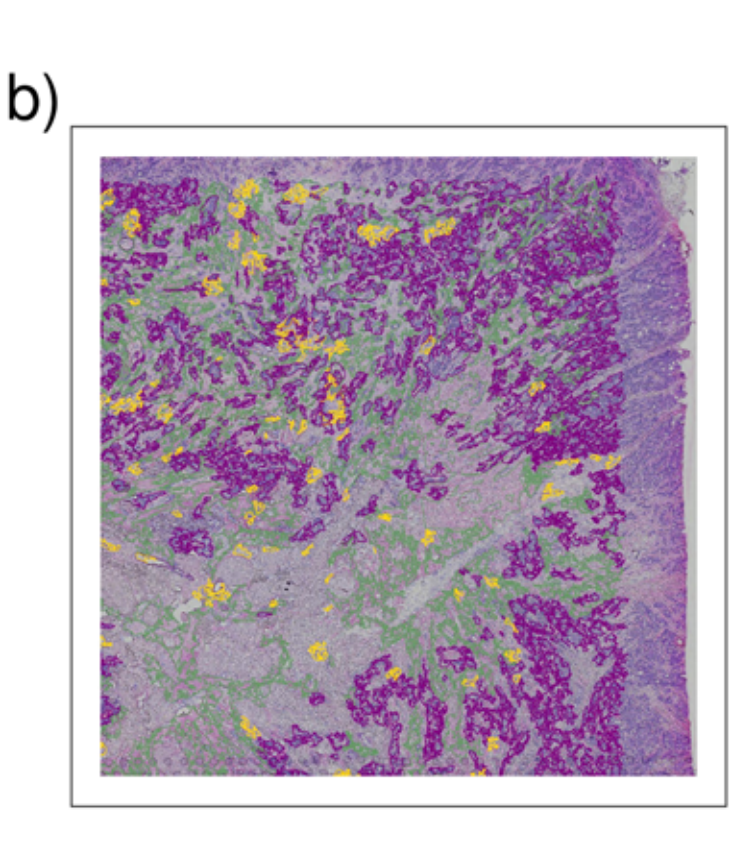

Wei R. et al. - 2022

Spatial charting of single-cell transcriptomes in tissues

Condition Dimension

N/A

Data Components

Biological Annotation

Data

Metadata

None

Modality

Sequencing-based

Resolution of observation

Functional tissue unit

Visualized Elements

Observation

Biological

Tissue

Abstraction

None

Chart Type

Histological image

Communicative/Contextualization

Annotation

Comparative Design

None

Layout

Spatial : Physical

Scalability Strategy

None (Item-level)

Where are tumor regions located within the spatial architecture of a tissue section?